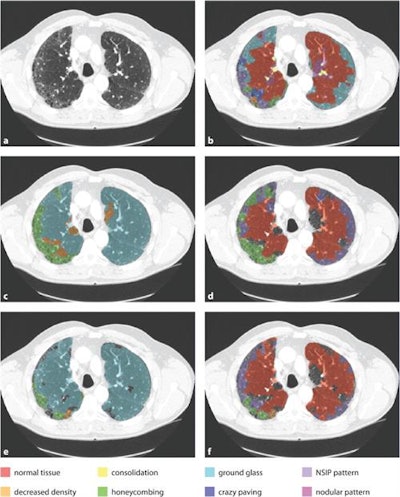

An example axial slice (a) that was annotated by observer A (c) and observer D (d), with low interobserver agreement; automatic classification results (b); interactive classification results after training on at least 50% of all VOIs in the scan annotated by observer A (e); and interactive classification results after training on at least 50% of all VOIs in the scan annotated by observer D (f).In their new study, Thessa Kockelkorn of the Images Science Institute at UMC Utrecht and colleagues developed one automatic and two interactive protocols for classification of abnormal lung textures. They tested these on scans of 10 patients who exhibited various types of lung disease and corresponding texture patterns. In each protocol, lung CT scans are segmented, and then subdivided into volumes-of-interest (VOIs) containing homogenous lung textures (Physics in Medicine and Biology, 20 July 2016, Vol. 61:16, pp. 5906-5924).

In the automatic method, the VOIs of one scan were labeled by an Extra-Trees classifier based on previously made annotations of the other scans. "In the interactive protocols," Kockelkorn explained, "an observer iteratively trains a classifier to distinguish different interstitial lung disease textures by correcting mistakes the classifier makes in a slice-by-slice manner." One interactive protocol started with training data from previous scans, the other from scratch.

The interactive protocols are considerably less time-consuming than manual labeling, Kockelkorn said, taking only 12 minutes for the user to label all the VOIs in a scan, compared with 45 minutes for manual classification.

In the automatic protocol, observers needed to relabel an average of 58% of the VOIs. In the interactive protocol without training data, the number of VOIs requiring relabeling decreased from 64% in the first slice to 13% by the second half of the scan, with 21% needing correction overall. With training data, the number of incorrectly labeled VOIs decreased from 56% to 13% in the second half, with only 20% requiring correction overall. Based on these results, Kockelkorn said: "The interactive approach we describe is a promising tool to make annotation of complete scans practically feasible."